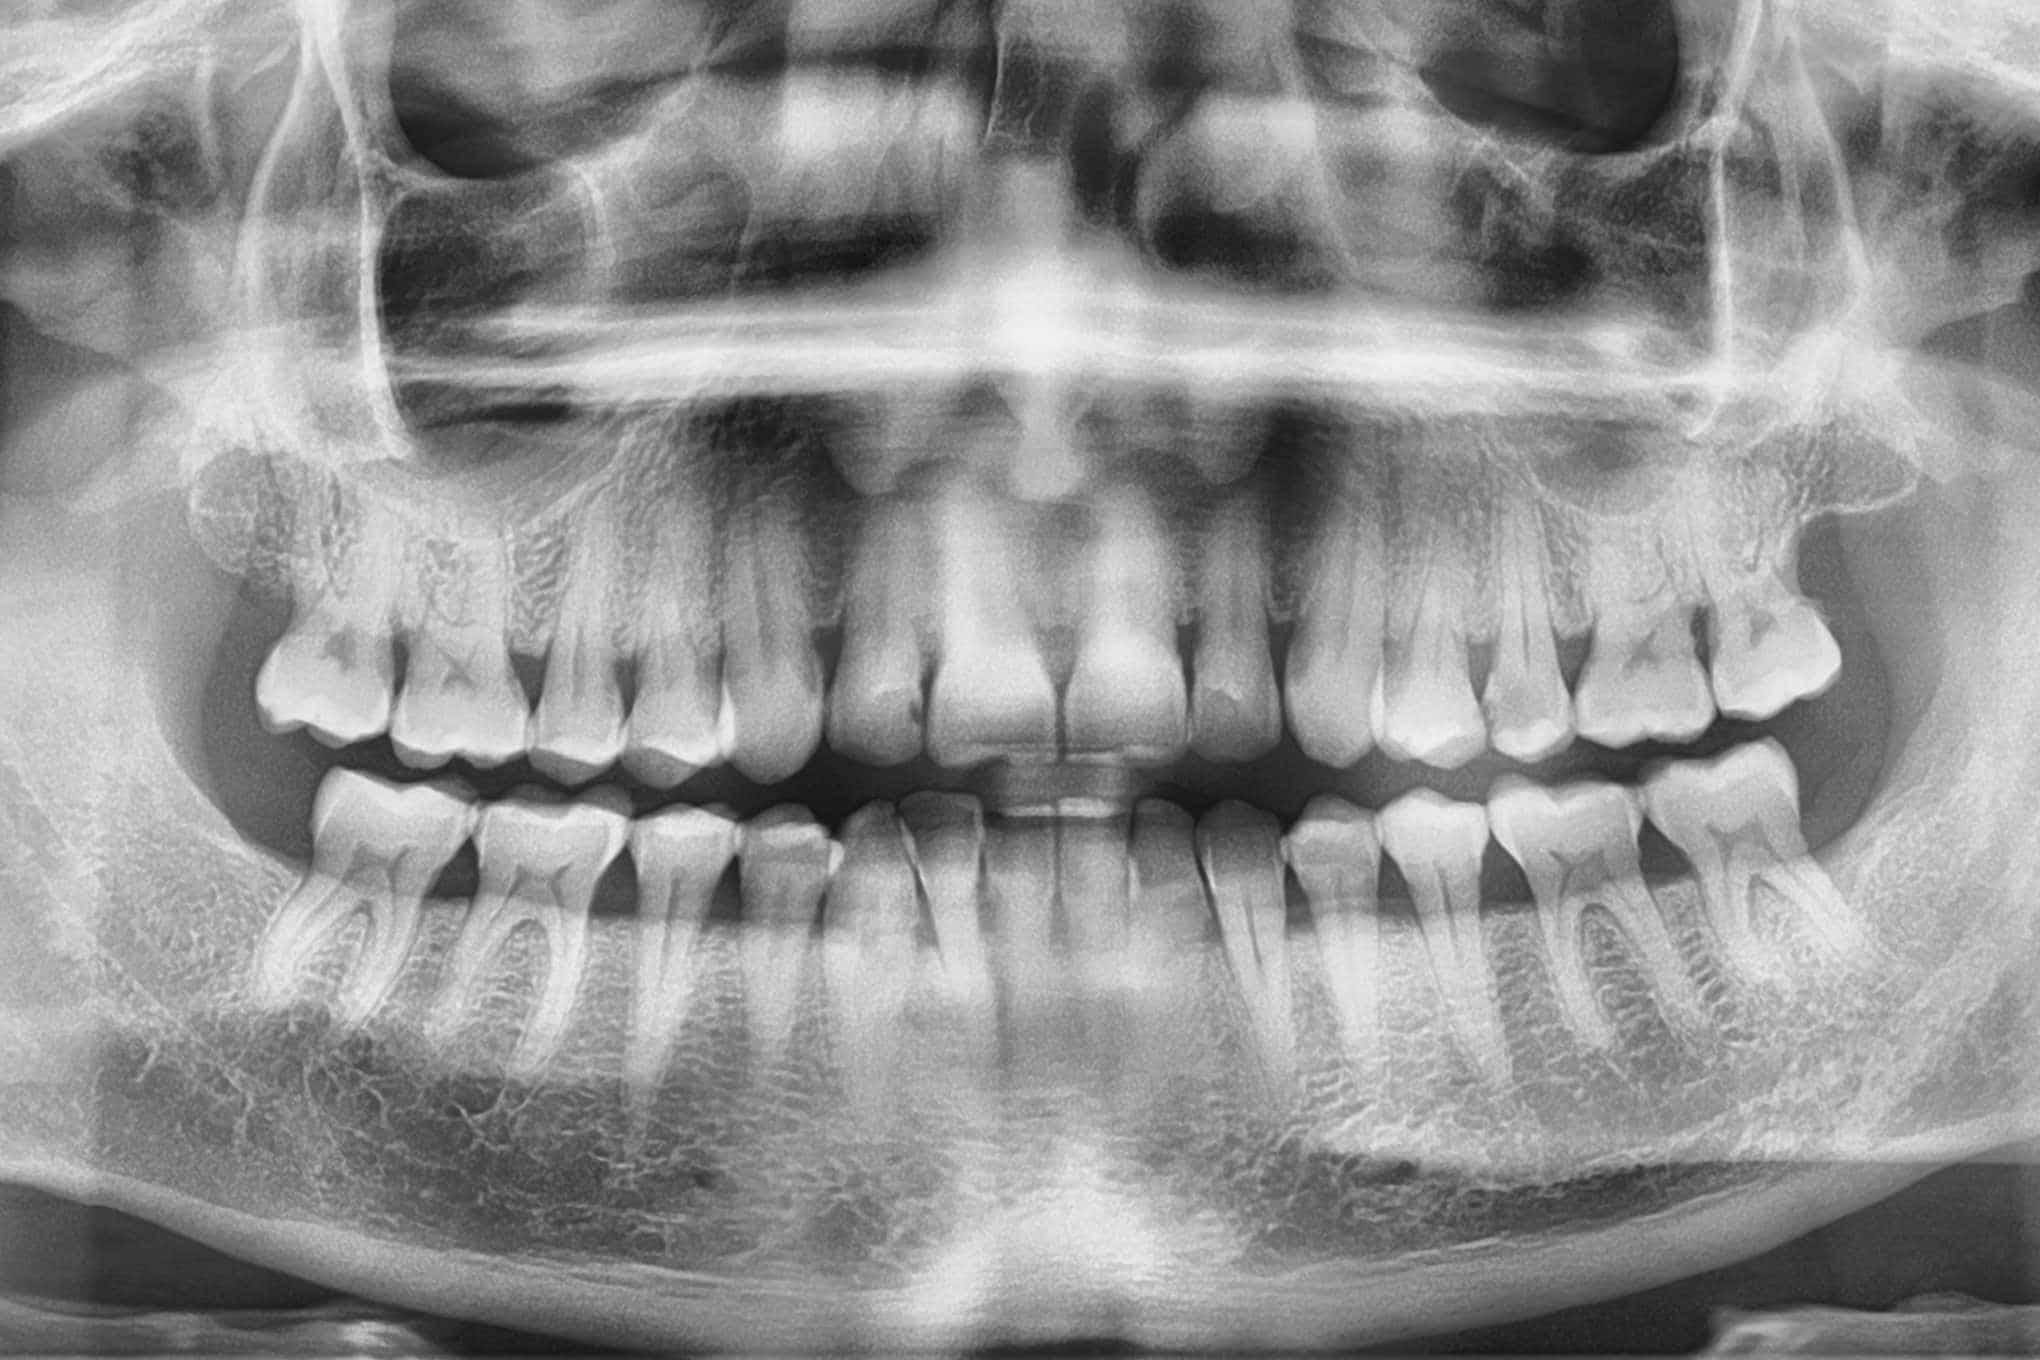

Kuukausimaksulla halpaa hammashoitoa?

Ei enää yllättäviä hammaslääkärikuluja!” Näin mainostaa helsinkiläinen hammaslääkäriasema Megaklinikka uutta, ”mullistavaa” kuukausihinnoitteluaan.